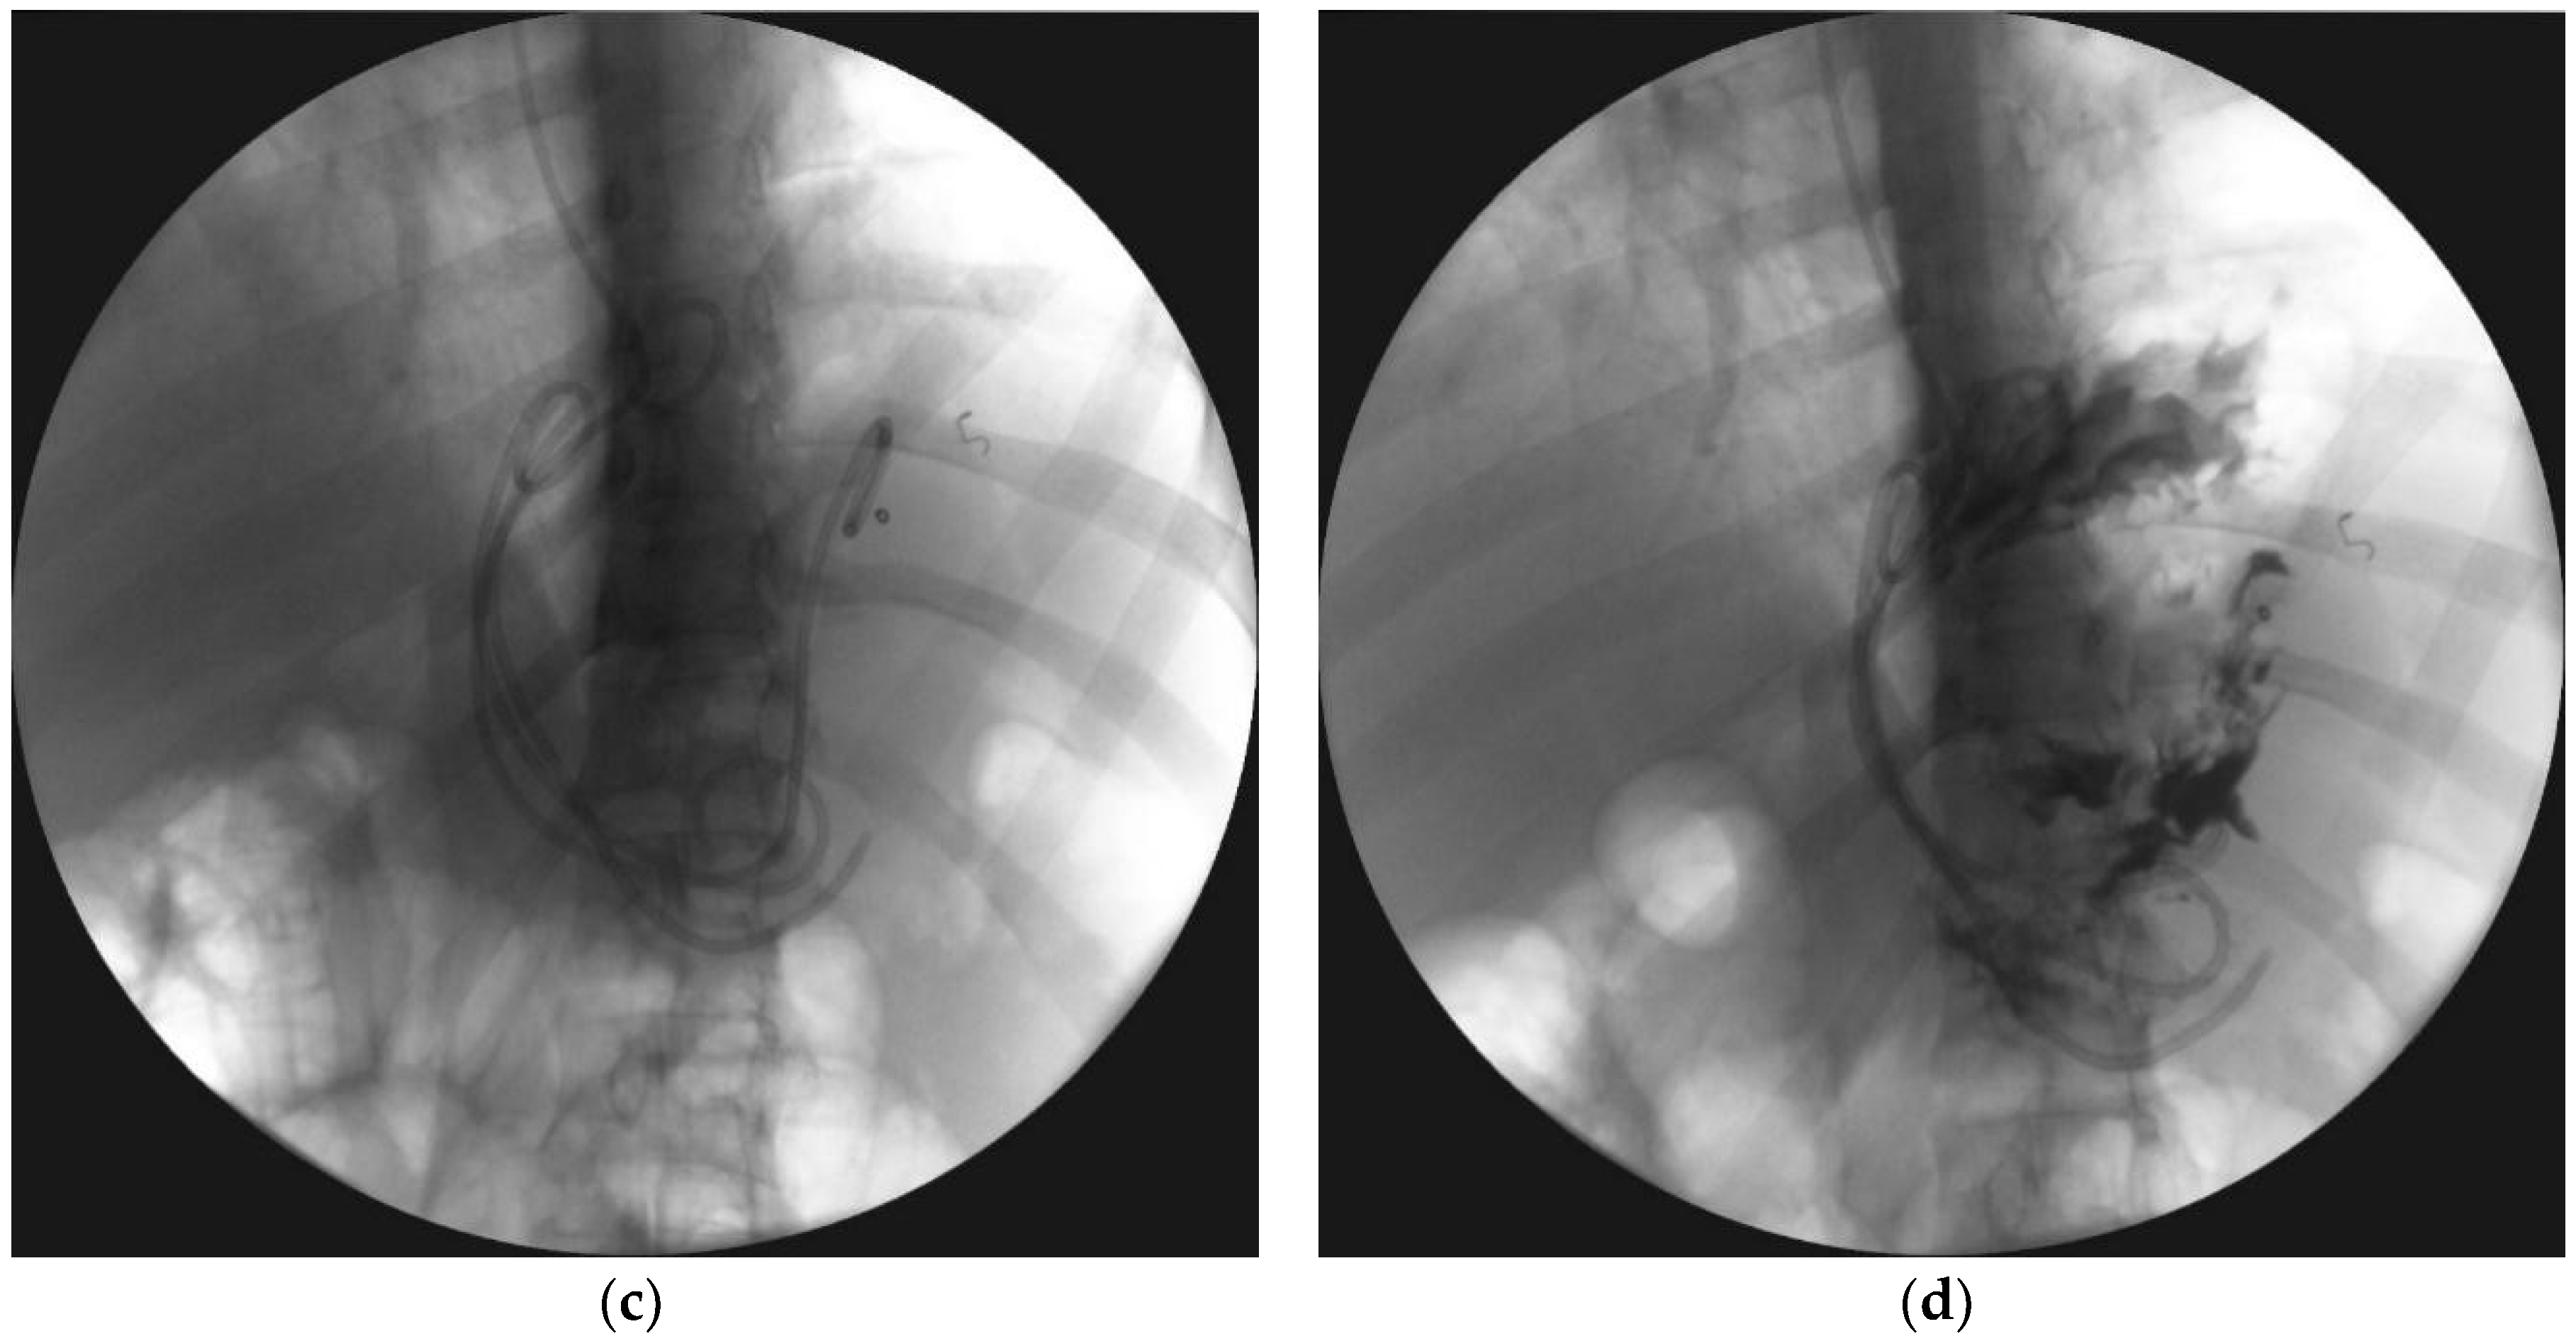

- Jagielski, M.; Smoczyński, M.; Studniarek, M.; Adrych, K. Endoscopic drainage combined with percutaneous drainage in treatment of walled-off pancreatic necrosis- a single center experience. Prz. Gastroenterol. 2018, 13, 137–142. [Google Scholar] [CrossRef] [PubMed]

| Endoscopic necrosectomy under fluoroscopic guidance (endoscopic debridement) | Procedure that enable to remove necrotic tissues from necrotic cavity through transmural fistula under fluoroscopy with use of various types of endoscopic tools. Indication for endoscopic debridement is WOPN containing poorly-liquefied necrotic tissues. |

| Direct endoscopic necrosectomy | Procedure accomplished via insertion of endoscope through the transmural fistula into the lumen of WOPN and direct removal of necrotic tissues under endoscopic view with use of different types of endoscopic tools. Direct endoscopic necrosectomy is usually technically easier to proceed during transmural drainage with use of SEMSs. Indications for direct endoscopic necrosectomy are extensive WOPN containing poorly-liquefied necrotic tissues without clinical improvement despite active transmural drainage. |

| Percutaneous drainage | Drainage enables to insert a drain transperitoneally or retroperitoneally into the lumen of necrotic cavity under control of ultrasonography or computed tomography and to flush the necrosis with saline solution through the percutaneous drain. This technique may be used as the only way to approach the necrosis or as additional approach (according to ‘step-up approach’ strategy). |